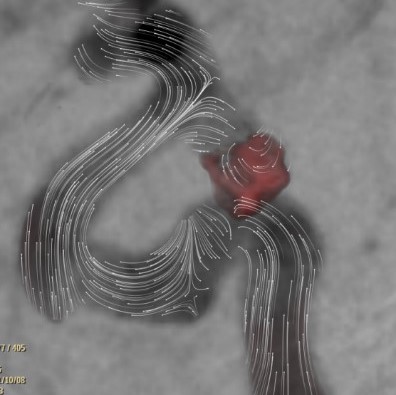

心房細動アブレーション治療(透視像)

心房細動アブレーション治療